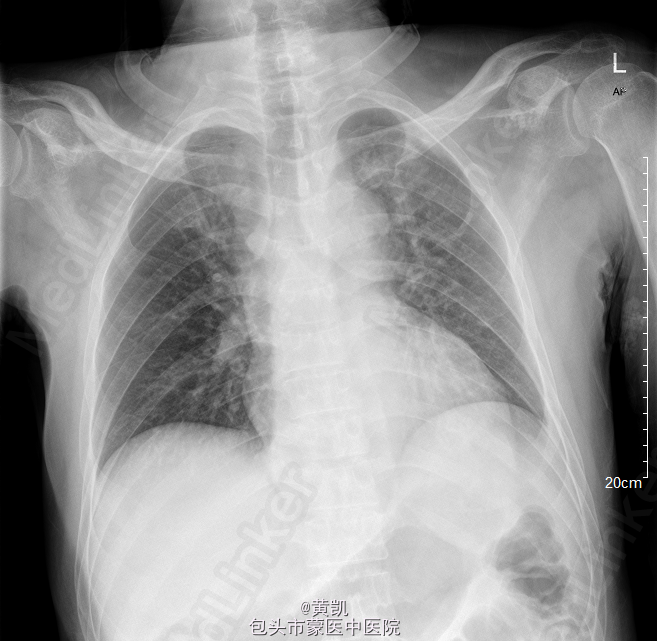

脊柱无明显畸形,颈椎压痛明显,双侧上肢远端肌力II级,近端肌力III,肌张力明显减低。左下肢肌力III级,右下肢肌力II级,肌张力明显减低,双侧Hoffman征阴性,巴氏征阴性,病理征阴性。MRI 2015-04-15:C3/4结核伴椎旁脓肿形成。 T8,T9,T10,T11,T12椎体结核伴椎旁脓肿形成。

初步诊断:1.颈椎结核 2.胸椎结核 3.2型糖尿病.处理:行“颈椎前路结合病灶清除植骨融合内固定术+取髂骨植骨术+颈椎后路内固定术”。